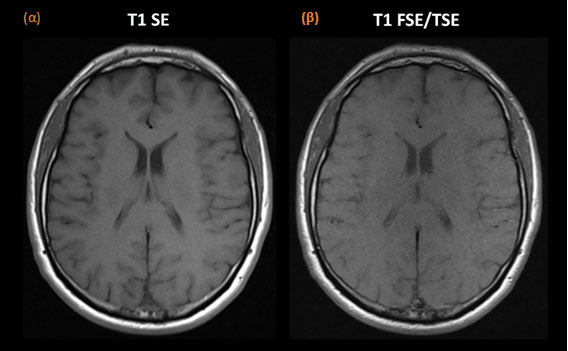

Για το σχηματισμό εικόνων βάρους Τ1 (Τ1 Weighting, T1W) απαιτείται χαμηλός χρόνος TR (μέχρι 700ms) και μικρός χρόνος ΤΕ (min μέχρι 15ms). Στις ακολουθίες βάρους Τ1 οι ιστοί με μεγάλο χρόνο χαλάρωσης Τ1 αναδεικνύονται σκοτεινοί, ενώ ιστοί με μικρό χρόνο χαλάρωσης Τ1 αναδεικνύονται φωτεινοί. Οι εικόνες βάρους Τ1 είναι χρήσιμες για ανάδειξη ανατομίας.